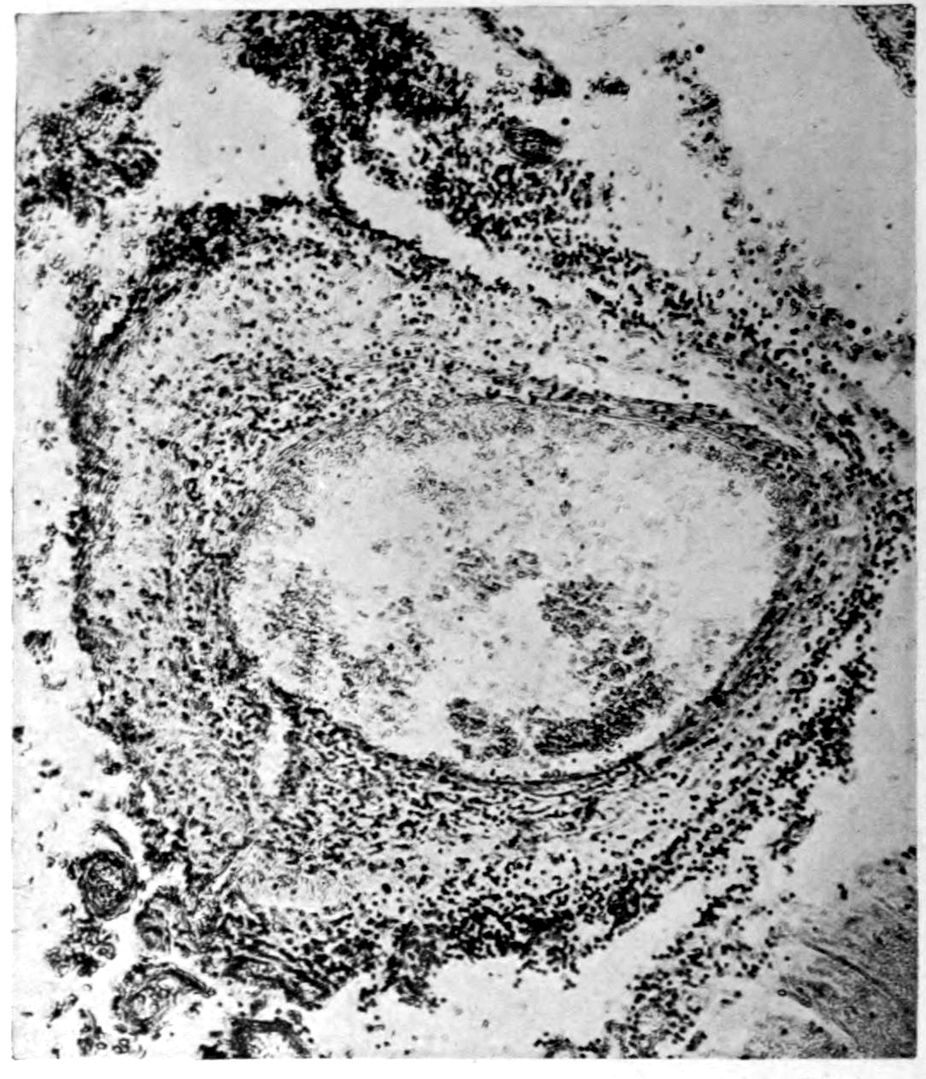

Apparent new formation of small blood vessel. Photographed by Dr. A. M. Barrett.

41Characteristic and constant in paretic neurosyphilis is the Plasmocytosis and Lymphocytosis, Perivascular in distribution about small cortical vessels. There is also a characteristic (though characteristically less prominent) Plasmocytosis and Lymphocytosis, Meningeal in distribution. The pleocytosis of the spinal fluid, almost constant though variable in amount in life, is an indicator of the meningeal picture and less directly of the parenchymatous picture.

Granular Ependymitis (“sanding” of ventricle floors) is characteristic and may be regarded as part of the parenchymatous picture. This ependymitis is an indicator how chemical changes could be readily produced at least in the ventricular fluids, since the limiting membranes of the nerve tissue are here subject to multiple breaks. The “sanding” is a neuroglia reaction to these multiple small breaks (Weigert’s explanation).